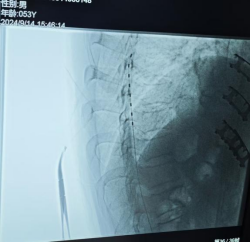

SCS电极植入影像

经与患者及家属的充分沟通,9月14日,熊鹏举团队为患者实施了脊髓电刺激手术,于T7-T9硬膜外腔植入1根脊髓电刺激电极。术中测试,电极位置覆盖良好,电刺激的酥麻感完全覆盖疼痛部位,手术非常顺利。术后当天,熊主任为患者开启刺激,经参数调试,患者能明显感觉到疼痛得到缓解,VAS评分也从9分降到4分。